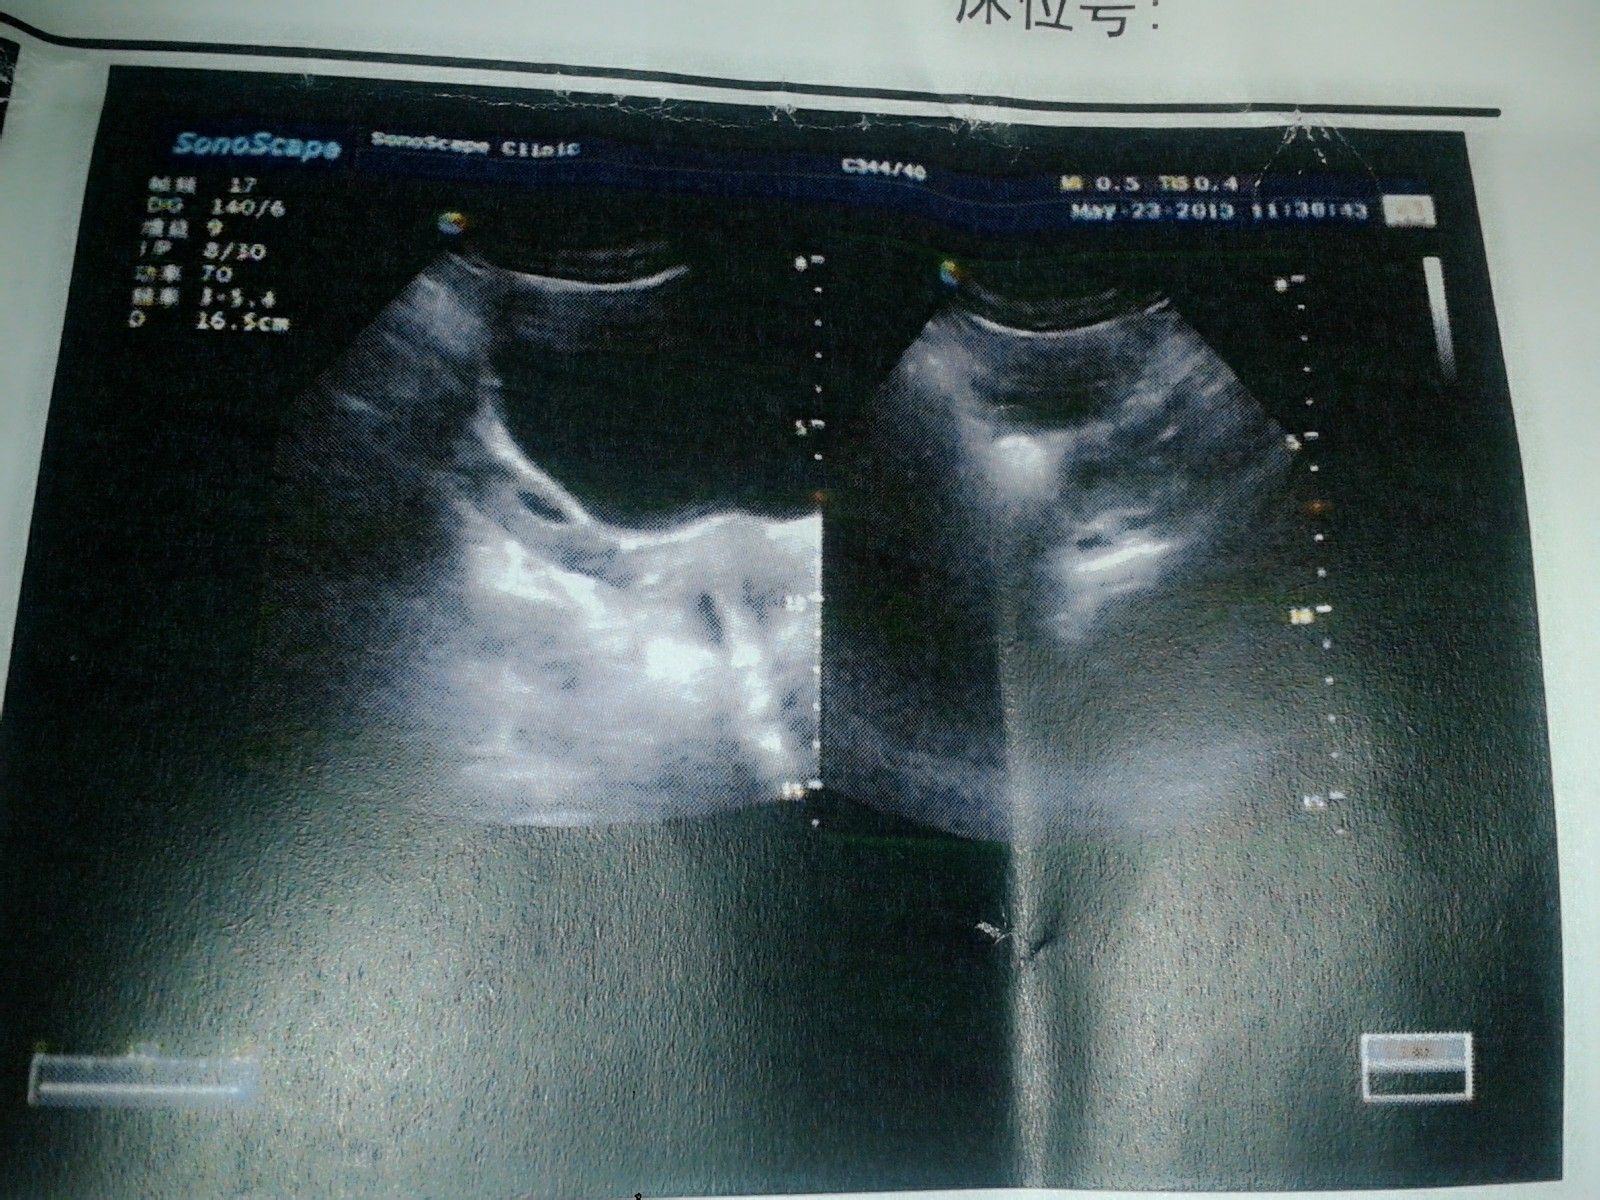

自然流产后一星期的B超报告,用做清宫吗?

病情描述:怀孕52天后自然流产,一周后复查报告子宫:前位,宫体大小约48×37×42mm,形态规则。肌壁回声均匀,宫腔线居中,内膜薄厚不均,较厚处7mm。右侧卵巢大小34×16mm,左侧卵巢大小30×26mm. 双侧附件未见明显异常。肚子偶尔会轻微隐痛,阴道留有咖色血与分泌物希望医生提供的帮助:我想知道现在到底用不用清宫,医生老是说观察观察看看,有有这个时间我就算做清宫都快恢复了,拖着也对身体不好。

从B超来看,没有发现有组织唉恨物,说明流的卫栋基本是干净的。 建议服用新化生颗粒和甲硝唑一周。 从这个来看,没有太大的清宫必要,毕竟清宫也是对子宫黏膜的一种伤害。 医生要求观察一下也是正确的,就是看看你串渐岩子宫内膜的恢复状况。